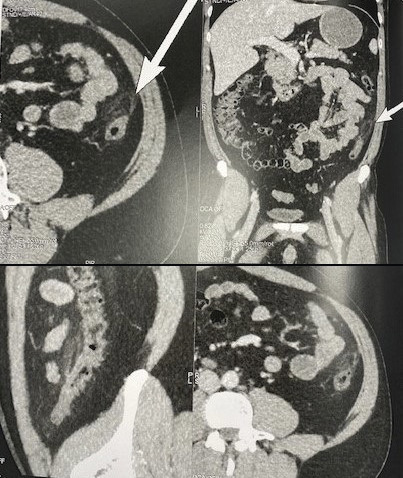

À l’examen clinique, on note une douleur augmentée à la palpation en fosse iliaque gauche. Le scanner abdominopelvien plaide en faveur d’une panniculite mésentérique (figure ).

La panniculite mésentérique idiopathique est évoquée devant la présence au scanner d’une pseudomasse hétérogène hyperdense au sein de la graisse mésentérique, sans ascite ni œdème sous-cutané. C’est un diagnostic d’élimination. Il convient en effet d’exclure un œdème mésentérique, une inflammation locale, une tuberculose péritonéale, une hémorragie, un lymphome, un neurofibrome, un lipome, un liposarcome…